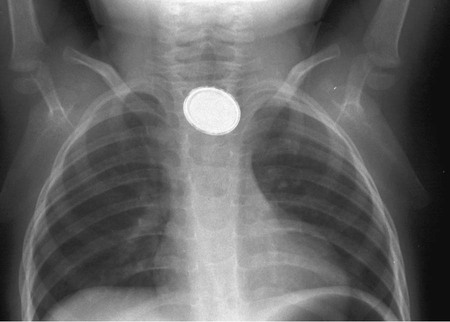

Evaluation of the child with a history of foreign body ingestion starts with plain anteroposterior radiographs of the neck, chest, and abdomen, along with lateral views of the neck and chest. The flat surface of a coin in the esophagus is seen on the anteroposterior view and the edge on the lateral view (Fig. 327-1). The reverse is true for coins lodged in the trachea; here, the edge is seen anteroposteriorly and the flat side is seen laterally. Disk batteries can look like coins (Fig. 327-2) and have a much higher risk of burns and necrosis (Fig. 327-3). Materials such as plastic, wood, glass, aluminum, and bones may be radiolucent; failure to visualize the object with plain films in a symptomatic patient warrants urgent endoscopy. CT scan with 3-dimensional reconstruction may increase the sensitivity of imaging a foreign body. Although barium contrast studies may be helpful in the occasional asymptomatic patient with negative plain films, their use is to be discouraged because of the potential of aspiration as well as making subsequent visualization and object removal more difficult.

In managing the child with an esophageal foreign body, it is important to assess risk for airway compromise and to obtain a chest CT scan and surgical consultation in cases of suspected airway perforation. Treatment of esophageal foreign bodies usually merits endoscopic visualization of the object and underlying mucosa and removal of the object using an appropriately designed foreign-body-retrieving accessory instrument through the endoscope, and with an endotracheal tube protecting the airway. Sharp objects in the esophagus, disk button batteries, or foreign bodies associated with respiratory symptoms mandate urgent removal. Button (disk) batteries, in particular, must be expediently removed because they can induce mucosal injury in as little as 1 hr of contact time and involve all esophageal layers within 4 hr (see Fig. 327-3). Asymptomatic blunt objects and coins lodged in the esophagus can be observed for up to 24 hr in anticipation of passage into the stomach. If there are no problems in handling secretions, meat impactions can be observed for up to 12 hr. In patients without prior esophageal surgeries, glucagon (0.05 mg/kg IV) can sometimes be useful in facilitating passage of distal esophageal food boluses by decreasing the lower esophageal sphincter pressure. The use of meat tenderizers or gas-forming agents can lead to perforation and are not recommended. An alternative technique for removing esophageal coins impacted for <24 hr, performed most safely by experienced radiology personnel, consists of passage of a Foley catheter beyond the coin at fluoroscopy, inflating the balloon, and then pulling the catheter and coin back simultaneously with the patient in a prone oblique position. Concerns about the lack of direct mucosal visualization and, when tracheal intubation is not used, the lack of airway protection prompt caution in the use of this technique. Bougienage of esophageal coins toward the stomach in selected uncomplicated pediatric cases has been suggested to be an effective, safe, and economical modality where endoscopy might not be routinely available.